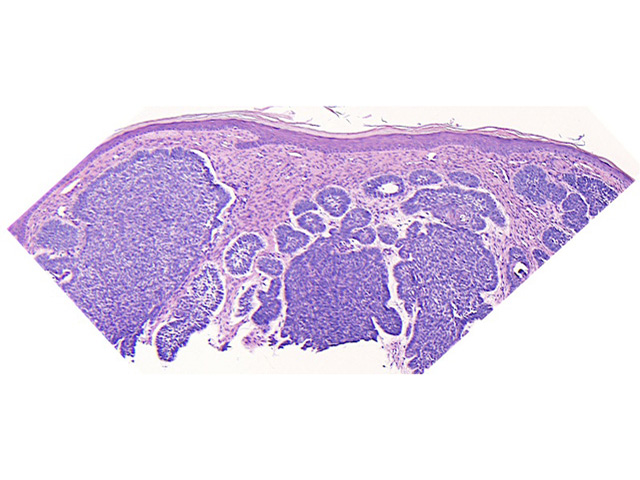

Histopathology of actinic keratosis

Vertical shadowing from surface scaling (OCT), same lesion

BCC on histopathology

OCT

Images courtesy of Dr Orit Markowitz. In the right hand example, the dark halo encompassing the BCC tumour on OCT (bottom) is a characteristic finding for BCC nests. This feature includes both the mucinous cleft and the peripheral palisading evident on histology sections (top).